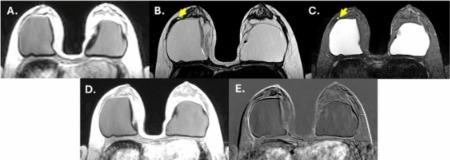

Penelitian ini dipublikasikan di Egyptian Journal of Radiology and Nuclear Medicine yang dipublikasikan pada Juni 2025 dengan judul “Accuracy of abbreviated breast magnetic resonance imaging protocols for primary tumor and post-treatment evaluation”. Studi ini melibatkan 205 pasien dengan total 277 lesi yang diperiksa menggunakan protokol MRI singkat berdurasi 10–11 menit, jauh lebih cepat dibandingkan MRI konvensional yang membutuhkan sekitar 25 menit. Hasil penelitian menunjukkan bahwa abbreviated MRI memiliki sensitivitas hingga 92% dan spesifisitas 89%, menandakan kemampuannya dalam membedakan antara lesi jinak dan ganas dengan akurasi yang tinggi.

Menurut Prof. Lina Choridah, metode abbreviated MRI sangat relevan diterapkan di fasilitas kesehatan dengan sumber daya terbatas karena dapat memangkas waktu pemeriksaan dan biaya secara signifikan. Ia menekankan bahwa pendekatan ini juga sangat efektif untuk mendeteksi kanker pada perempuan berusia muda dengan jaringan payudara padat, yang umumnya sulit dievaluasi menggunakan metode mammografi. Penelitian ini mengungkap bahwa kelompok usia di bawah 40 tahun memiliki proporsi kasus kanker payudara yang cukup tinggi, sehingga kebutuhan akan metode diagnostik yang lebih efisien dan sensitif menjadi semakin mendesak.